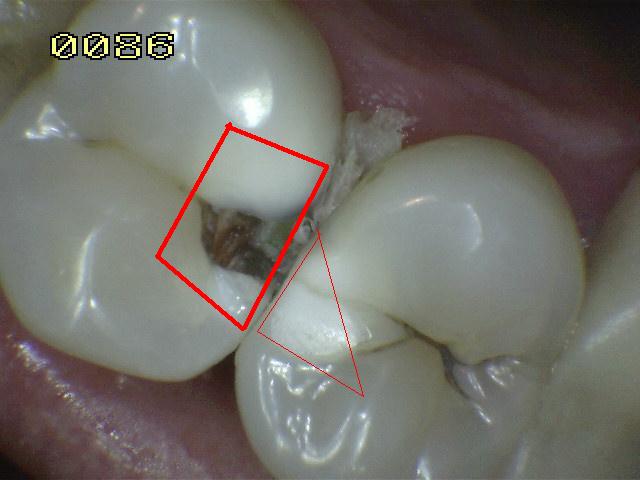

Sistema Internacional para la Detección y Evaluación de Caries (ICDAS)

¿Determine los códigos pertinentes a cada imagen?

Click en el hipervínculo: Para comparar el resultado de su diagnóstico